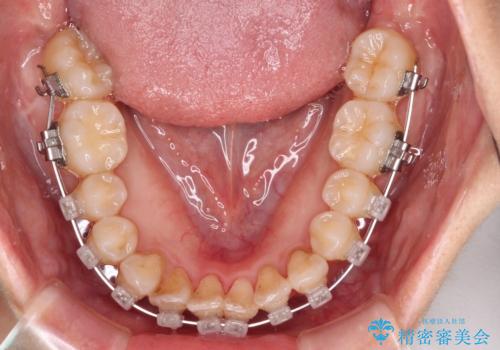

捻れた前歯をできるだけ短期間で 表側のワイヤー矯正

- クリアブラケット

- 上下前歯のねじれを気にして来院された患者様です。

ワイヤー矯正でもマウスピース矯正でも対応可能でしたが、マウスピース矯正の自己管理が面倒であること、上顎前歯の捻転が著しいことから、ワイヤー矯正での治療を希望されました。

日々前歯の捻れが解消されていくので、歯の動きを楽しみながら矯正治療を進めることができました。